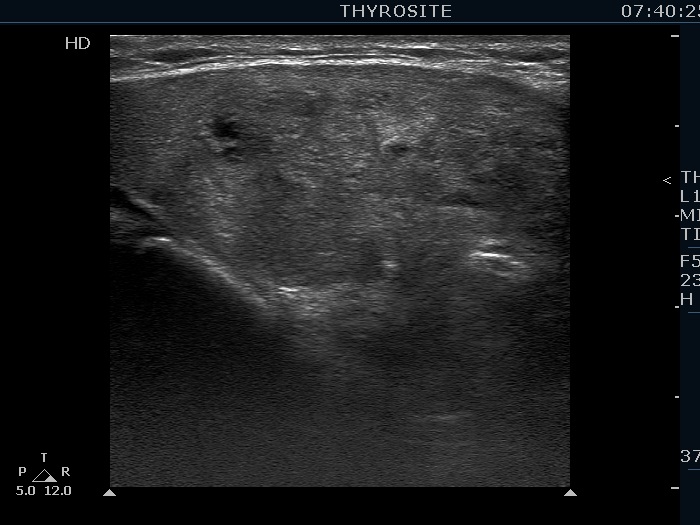

Second examination (second row of images):

Clinical presentation: The patient was referred for a follow-up examination.

Palpation remained unchanged.

Functional state: euthyroidism with TSH 2.11 mIU/L.

Ultrasonography. Both the size and the presentation of the nodules remained unchanged.

We may have doubt about the origin of echogenic figures, if we rely on the analysis of images. However, video proves that most of these granules and lines are related to tiny ventral cystic areas. It means that they are back wall cystic figures caused by posterior enhancement. Moreover, it is worth taking into account that the nodule lacks other suspicious characteristics which would be an unusual finding in the event of such large number of microcalcifications.

This study illustrates the difficulty of interpretation of hyperechogenic granules. In such cases the thorough analysis of the video is of much greater help than that of the images.